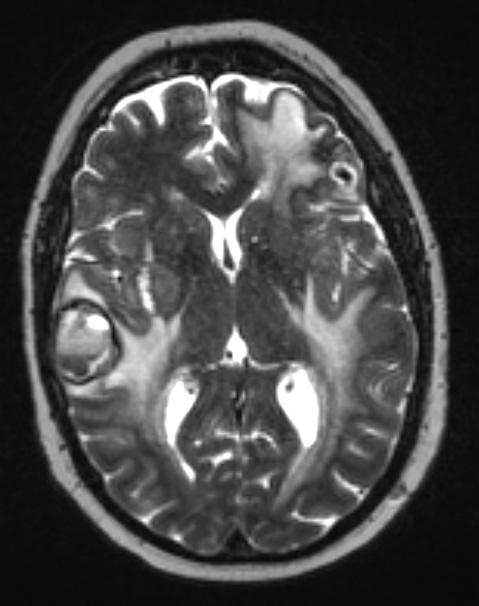

2A3 Metastases, melanoma (Case 2) T2 W 1 - Copy

Multiple metastases are seen in T2-weighted contrast applied MRI scan..